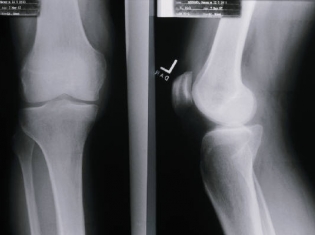

(RxWiki News) A new hip or knee may be what you need to set yourself free from arthritis pain. Many implants are made of metal. So, what happens if you are allergic to metal?

Patients should be tested for metal allergies before undergoing surgery to implant a prosthetic joint or bone. If a patient is tested for metal allergies after implantation, the surgeon and patient should decide together whether to remove the implant.